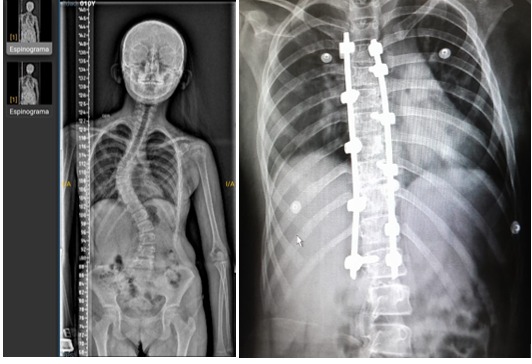

Escoliosis 7 Niveles – Sistema Legacy Medtronic

Procedimiento de corrección de escoliosis de columna con Sistema Legacy de Medtronic

La cirugía de escoliosis se realiza cuando se produce una pérdida del eje de orientación de la columna, que puede estar asociada a deformidades congénitas con neuropatía.

El caso que presentamos involucraba a una paciente mujer Victoria M., pediátrica, de 11 años y contextura pequeña. La afectación mayoritaria se localizaba en el segmento torácico, donde la pérdida de orientación vertebral, aunque presente, aún no afectaba la marcha de la paciente, pero comprometía su postura y aumentaba el riesgo de futuras complicaciones respiratorias.

La Cirugía: El objetivo era reorientar o restablecer la orientación anatómico-funcional de la columna. La planificación preoperatoria implicó medir ángulos y la dirección de la corrección, para luego reproducirla en la colocación de los implantes.

Implantación: Se utilizaron tornillos pediculares poliaxiales y monoaxiales, junto con ganchos pediculares y laminares, complementados con barras de titanio que se colocaron longitudinalmente y en paralelo a las apófisis espinosas.

Caso Particular de la Paciente M. Victoria: Se realizó una instrumentación en 7 niveles utilizando tornillos poliaxiales, monoaxiales de bajo perfil y ganchos laminares correspondientes al sistema Legacy de Medtronic. Este sistema ofrece dos opciones de desrotación: una manual individual y otra segmentaria mediante dispositivos denominados torretas, según las necesidades del paciente.

La intervención se llevó a cabo sin complicaciones en la provincia de San Miguel de Tucumán. La paciente se despertó de manera positiva con movilización inmediata de los miembros inferiores y se recuperó sin alteraciones en la unidad de cuidados intensivos. Al día siguiente, pudo incorporarse para iniciar la adaptación a su nueva postura.